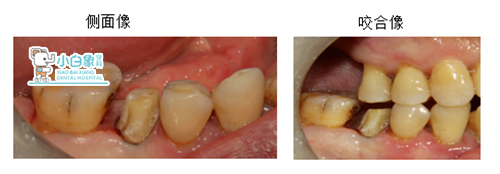

检查:45远中邻合面龋坏达牙本质深层,叩诊(-),温度试验敏感,牙龈无红肿。

46牙冠邻面见硬龋,探诊光滑,温度试验正常,牙龈无红肿。16 17 缺失,牙龈无红肿。

治疗:45必兰麻醉下去腐,开髓揭顶,预备根管一根,根长19mm,荡洗,隔湿干燥,根充,制备桩道,树脂粘结红色纤维桩,预备全冠,扫像,设计,粘结全冠,调合。